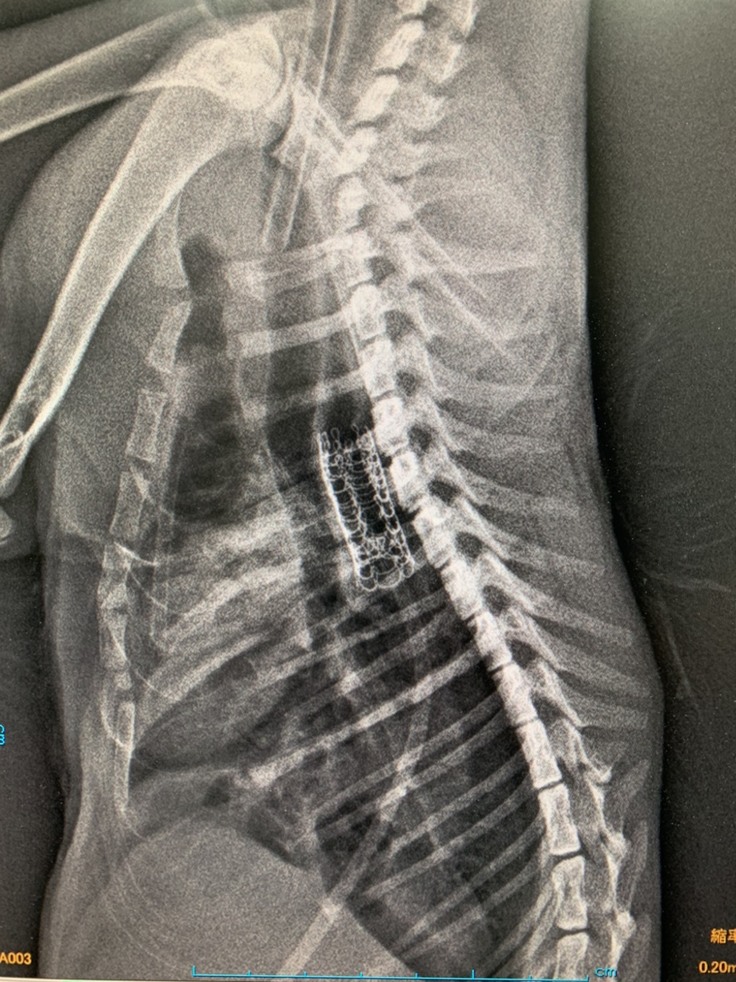

中央のモジャモジャとしたものがステントになります。

ちょうど心臓の上で処置も難しかったそうです。

今のところ、ステントが動いたりはしていないということで一安心です。